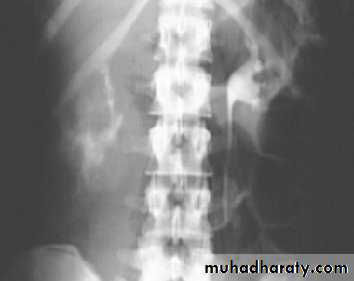

Horse shoe kidney -Kidneys may fail to separate.

-Almost invariably the lower poles remain fused.

-The kidneys axes are more parallel to the spine and malrotated.

-Diagnosis can be made by plain x-ray in some cases.

-US, CT scan and MRI can better demonstrate the anatomy and morphology hence the diagnosis.

-May be an incidental finding.

-PUJ obstruction and calculi formation are common .

IVU shows

1. The kidneys at low position .

2.Close to the spine with long axis parallel to the spine .

3. Malrotation manifested by medially directed calyces.

4- The renal pelvis and ureters are anterior and lateral in position .